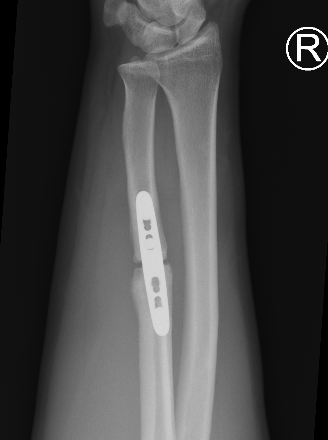

Compression plating

Ulna Intramedullary WireUlna Plating

AO foundation ulna plating

Ulna nonunion after plating